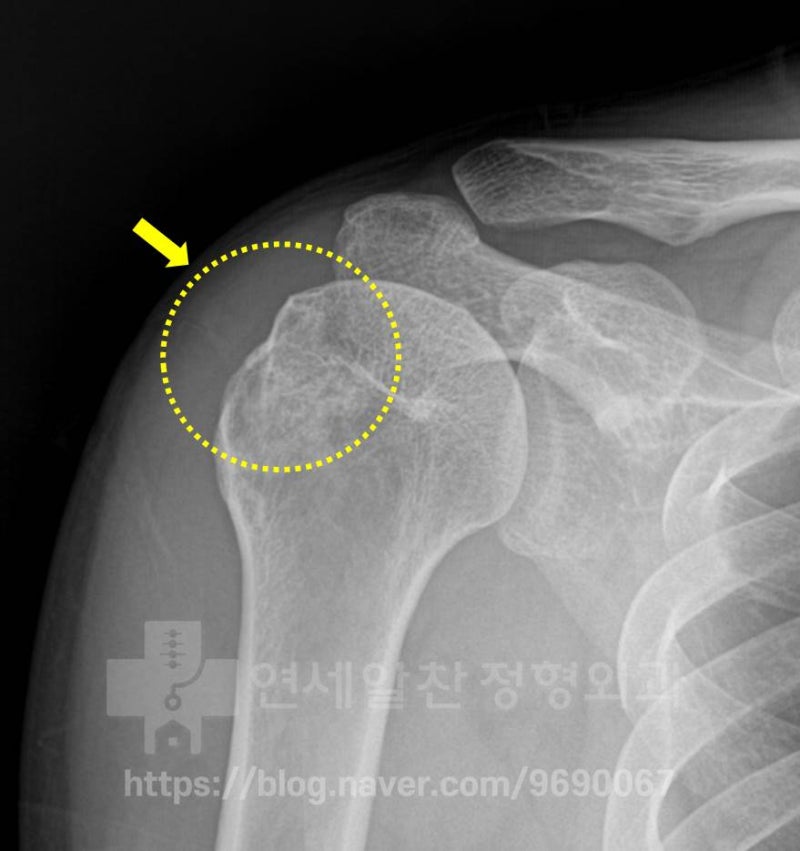

노란색 점선으로 표시된 부위를 보면 상완골의 대결절 부위가 정상적이지 않고 뭔가 손상된 것 처럼 보입니다.

다른 MRI 를 보면 빨간색 점선으로 표시된 부위에서 대결절 부위의 불규칙한 면이 관찰되고 있습니다. 하지만 극상근의 약화는 관찰되나 파열 소견은 관찰되지 않습니다. 환자의 수상 기전과 상기의 검사들은 보았을 때 석회성 건염 보다는 대결절 골절이 발생되었고 그로 인한 불유합이 발생된 것으로 판단됩니다. 첫번째로 가장 안타까운 것은 최초 수상 당시 바로 치료를 제대로 했다면 (이정도의 손상이라면 대결절 골절에 대한 수술적 치료) 지금은 정상적으로 생활하고 운동을 할 수 있었을 것이라 생각됩니다. 그럼 이때 수술한 영상을 확인해 보겠습니다.